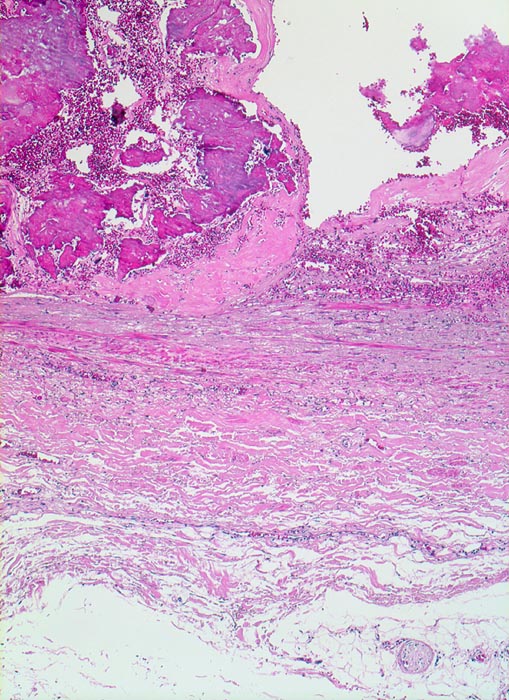

Morphologie:

Die Atherosklerose befällt Arterien vom elastischen Typ und die grossen und mittelgrossen Arterien vom muskulären Typ. Die früheste Läsion, der Lipidstreifen, besteht aus einer fokalen Akkumulation von Lymphozyten und glatten Muskelzellen und von Serumlipoprotein in Makrophagen der Intima (> 5267). Zirkulierende Monozyten infiltrieren die Intima, nehmen alteriertes LDL Cholesterin auf und wandeln sich dadurch in Schaumzellen um. Diese Läsion kann sich durch zunehmende Lipidakkumulation und Migration sowie Proliferation von Myofibroblasten zum Präatherom mit wenig extrazellulären Lipidablagerungen und schliesslich zum Atherom (> 9003) mit zentral konfluierten extrazellulären Lipidmassen (> 9004) und nekrotischem Detritus weiterentwickeln. Die eingewanderten Mediamyozyten produzieren extrazelluläre Matrix, welche über dem Atheromkern aus extrazellulärem Lipid, Schaumzellen, Kalziumsalzen und Zellschutt eine fibröse Deckplatte bildet. Die atheromatöse Plaque kann narbig umgebaut werden, dystroph verkalken und konsolidieren oder zu einer komplizierten Plaque fortschreiten. Komplizierte Läsionen sind charakterisiert durch Ulzeration, Thrombose oder Plaqueeinblutungen. Bei einer Verletzung des Endothels oder einer Ruptur der fibrösen Deckplatte kommt der thrombogene Inhalt des Lipidkerns in Kontakt mit dem zirkulierenden Blut und es bildet sich eine Gefässthrombose. Wiederholte Rupturen mit nachfolgender Organisation der Thrombose vergrössern die Plaque und führen zu einer zunehmenden Gefässeinengung. Bei langsam gewachsenen schweren Stenosen bildet sich oftmals ein guter Kollateralkreislauf aus, welcher bei plötzlichem Gefässverschluss einen Infarkt im Versorgungsgebiet der verschlossenen Arterie verhindern kann. Grosse inter- und intraindividuelle Unterschiede bezüglich der relativen Anteile von weichen atheromatösen und derben fibrotischen bzw. verkalkten (> 4557) Bestandteilen der Plaques bestimmen wesentlich die Stabilität bzw. Vulnerabilität der Läsionen. Der Lipidanteil liegt bei rupturierten Plaques generell höher als bei Plaques mit intakter fibröser Deckplatte.

Morphologische Merkmale:

• Intimafibrose mit fokalen grobscholligen(dystrophen) Verkalkungen und Einblutungen in der unteren Hälfte des Arterienquerschnitts.

• Fibröse bindegewebige Deckplatte über dem Atheromkern

• Atherome in der Intima mit zentraler Nekrose, Cholesterinkristallen, Entzündungszellen und gelben Hämosiderinablagerungen oder Einblutungen.

• Partielle Zerstörung der Lamina elastica interna.

• Atrophie der glatten Muskulatur der Media.